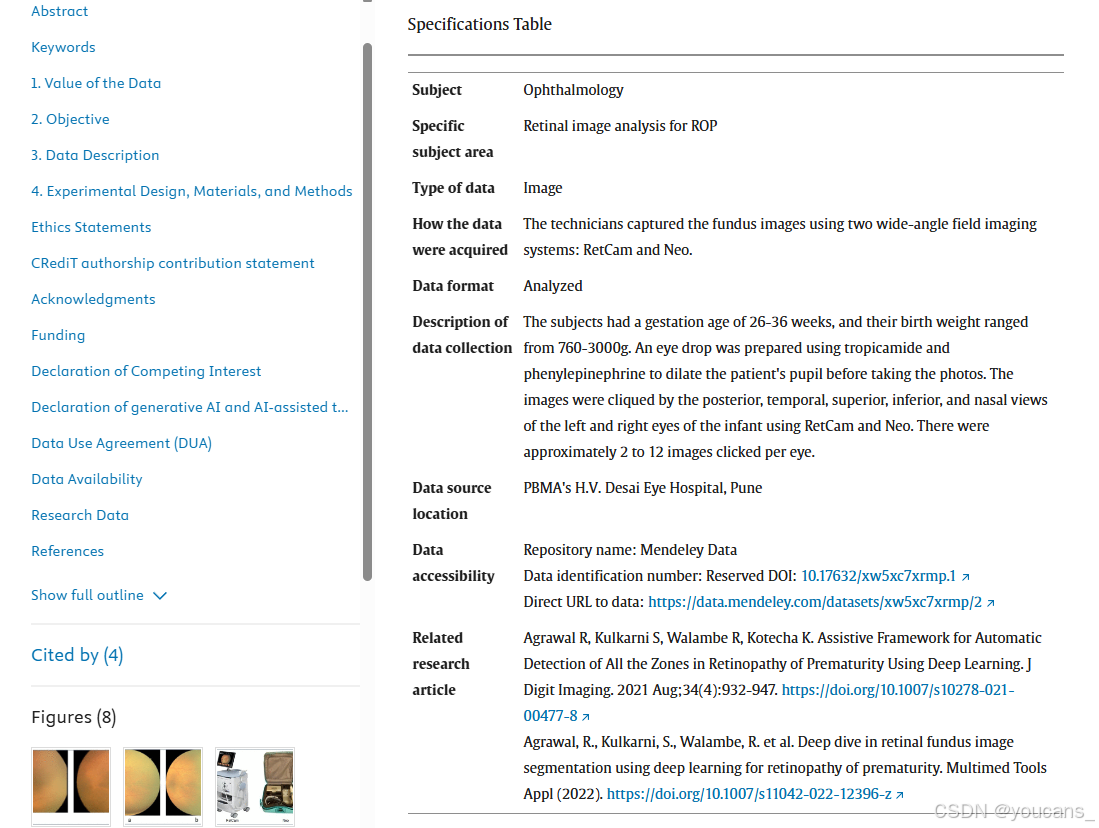

4.1 数据采集

受试者是妊娠26至36周的早产婴儿,体重不超过3000克。他们的个人信息会严格保密,并获得了父母的书面知情同意,将数据用于研究目的。

在图像采集之前,使用滴眼液(稀释的苯肾上腺素和托品酰胺)来扩张瞳孔。每只眼睛滴三次眼药水,间隔10分钟。第三滴眼药水后停止喂养婴儿。

使用 RetCam 和 Neo 获取婴儿每只眼睛的后视(posterior)、颞视(temporal)、上视(superior)、下视(inferior)和鼻视(nasal)图像。

每只眼睛采集了大约 2 到12张图像,从1100名患者中采集了10,570张RetCam图像和8,280张Neo图像。

RetCam 拍摄的图像分辨率为 640×480 像素,以.png格式存储,图像大小约为623KB;而 Neo 拍摄的图像分辨率是 2040×2040 像素,以.jpeg格式存储,图像大小约为 223KB。